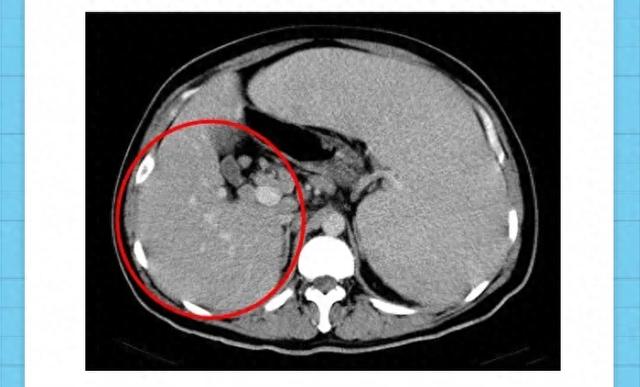

胆囊息肉最佳治疗方法

1、胆囊息肉的最佳治疗方法需根据息肉大小及合并症状综合判断,具体如下一需手术治疗的情况若胆囊息肉在彩超报告中显示直径达到1cm,且合并以下任一条件时,建议积极进行手术治疗1合并胆囊结石结石可能刺激息肉生长或引发胆囊炎...